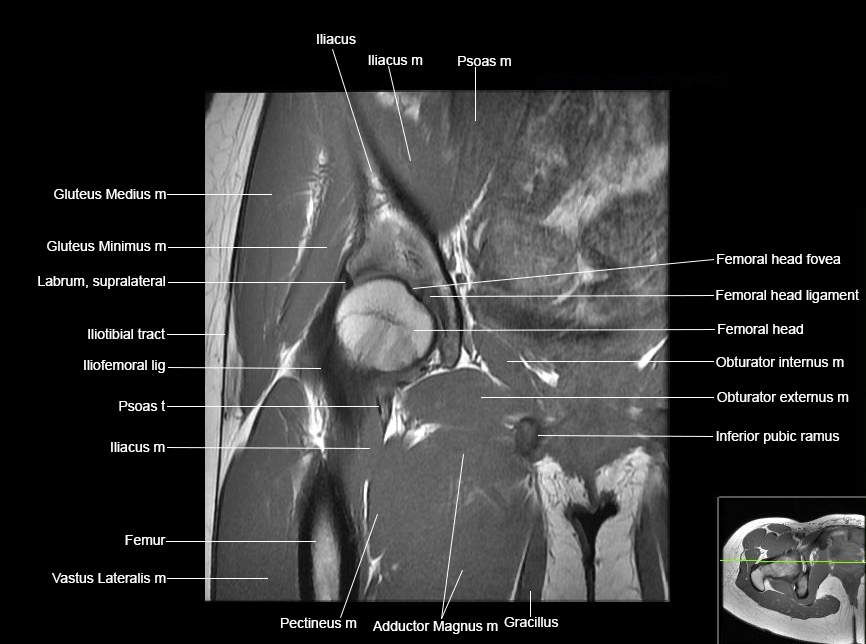

Hip

Basic Hip MRI

MRI Hip Anatomy

Scroll using the mouse wheel or the arrows